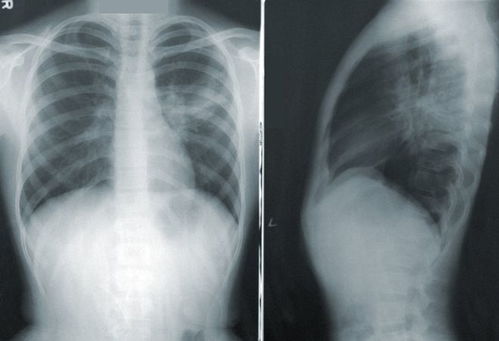

靶向治疗的效果并非一成不变,它需要不断地进行评估和调整。医生会通过影像学检查、肿瘤标志物水平检测以及基因检测等方式,来评估治疗的效果。由于不同患者对药物的敏感性存在较大的差异,医生会根据每个患者的具体情况,制定个性化的治疗方案。